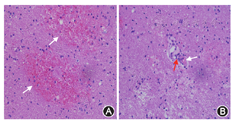

例1 患者女性,35岁,主因"发现颅内占位10年"于2015年5月19日来我院就诊。患者于10年前自觉左侧肢体无力,在当地医院查头颅CT及MRI提示:右颞顶巨大囊性占位,双侧基底节区多发钙化,于当地医院行颞顶占位切除术,术后分别在当地医院、首都医科大学宣武医院、首都医科大学附属北京天坛医院行病理学检查,结果未能明确病变性质,术后未再进行其他治疗,症状好转。5年前复查头颅MRI提示:右枕、左额、左枕分别出现长T1、长T2信号病变,双侧基底节区多钙化,仍无不适主诉,未进一步治疗。5个月前出现间断性周身乏力,复查头颅MRI提示:右枕部占位性病变明显增大,周围组织压迫明显,强化不明显。本次为手术入院。既往史:体健。无家族遗传史。神经科体检无阳性定位体征。眼底检查未见异常。头颅CT:双侧底节区可见钙化灶,双侧脑白质低密度灶。头颅MRI:左侧额叶、右顶叶可见多发囊状长T1、长T2信号,部分边缘可见结节样等T1、稍短T2信号,双侧基底节区可见散发点片状稍短T1、稍短T2信号,周边可见大片稍长T1、稍长T2信号,DWI见囊内稍受限信号,增强扫描可见多发结节样、条状及环形强化(图1)。右侧侧脑室受压,中线结构向左侧移位。病理检查:血管瘤样增生,可见充血、出血,血管间隙可见含铁血红素;血管变性充血,周围可见铁环(图2)。

例2 患者女性,20岁,主因"头痛2周"于2015年9月3日入我院。患者2周前出现头痛,双侧额、颞部胀痛,视觉模拟量表(Visual Analogue Scale,VAS)评分为5~6分,每次疼痛持续3~4 min,每半小时发作1次,1 d约头痛30~40次,站立时加重,卧位后略有减轻。头痛进行性加重,2 d前头痛难以忍受,VAS评分达10分,恶心、呕吐,为非喷射状呕吐。当地医院行头颅CT检查可见"左侧半球内有类圆形占位,密度不均,周围伴有广泛水肿,中线结构移位;右侧半球内可见囊性病变,双侧底节区不对称钙化。予以甘露醇脱水降颅压治疗,症状稍缓解。1 d前行头颅MRI+增强:左侧额颞叶皮质下有类圆形占位,内可看到短T1、长T2的不均匀混杂信号,DWI内高信号,增强可见环形及不均匀强化,周围明显水肿,右侧半球内可见囊性病变。为进一步治疗,转入我院住院治疗。既往史:间断额颞部头痛病史5年,呈胀痛,VAS评分3分,每次疼约半小时,1年发作3~4次。4岁时有头部外伤史,未遗留后遗症。无家族遗传病史。体检:意识清楚,计算力86-7=?,双侧肢体腱反射活跃,双侧霍夫曼征阳性,双侧查多克征阳性,口轮匝肌反射阳性,余均正常。眼底检查未见异常。头颅CT示双侧底节区多发钙化灶,脑白质低密度灶;头颅MRI示左侧额叶、右侧顶叶囊性占位,囊内呈长T2、长T1信号,FLAIR高信号,DWI示左侧额叶呈块状弥散受限;囊壁有环形强化,局部结节状强化;磁敏感加权成像示囊内有出血,双侧脑白质内有散在出血小灶;灌注扫描示脑白质变性和囊肿区低灌注;波谱分析示囊壁强化区胆碱峰不高(图3)。病理结果:可见出血区及血管纤维素样变性扩张,周围组织结构疏松(图4)。

LCC典型病理改变主要在囊性病变囊壁及周围。本文例1在第1次手术治疗后未见典型病理改变,难以明确诊断;例2经立体定向取活体组织检查未见明确典型病理病变,可能因为未取到囊壁及周围。本文例1病理改变为小血管呈瘤样增生,血管壁呈纤维素样变性,周围有出血和钙化、铁沉积。例2可能取到脑白质变性区,主要可见脑白质疏松,局部有坏死。结合文献报道及例1病理结果,LCC属于小血管病变,其病变后导致局部缺血、缺氧症状,并产生脑组织变性,局部有钙化灶和囊肿形成[1,6,7]。